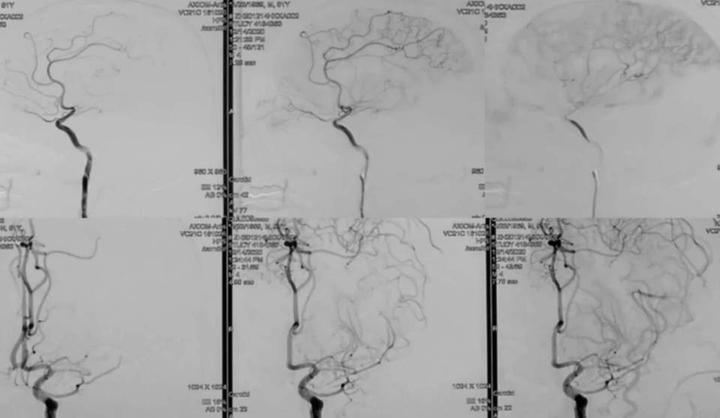

1、 语言和肢体障碍术后明显改善

3、左侧豆纹动脉显影及灌注明显改善,降低了再次基底节区脑梗塞的风险